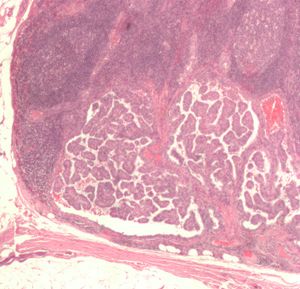

Thyroid papillary carcinoma histopathology (4).jpg

صورة مجهرية (عرض عالي الطاقة) من حليمي سرطان الغدة الدرقية مما يدل على ملامح التشخيص (المقاصة النووية ونوى المتداخلة). صبغة الهيماتوكسيلين والأيوزين.